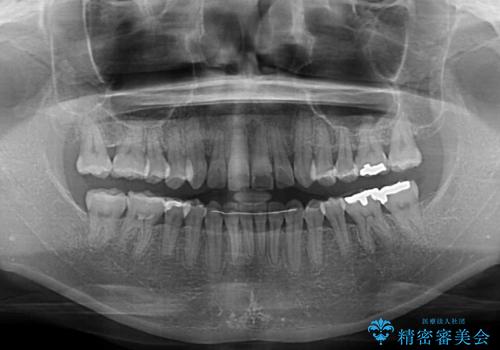

矯正治療の後戻り インビザライン・ライトによる矯正治療

- 矯正治療の後戻りを気にして来院された患者様です。

後戻りは軽微であったので、インビザライン・ライトにより矯正治療を行うこととしました。